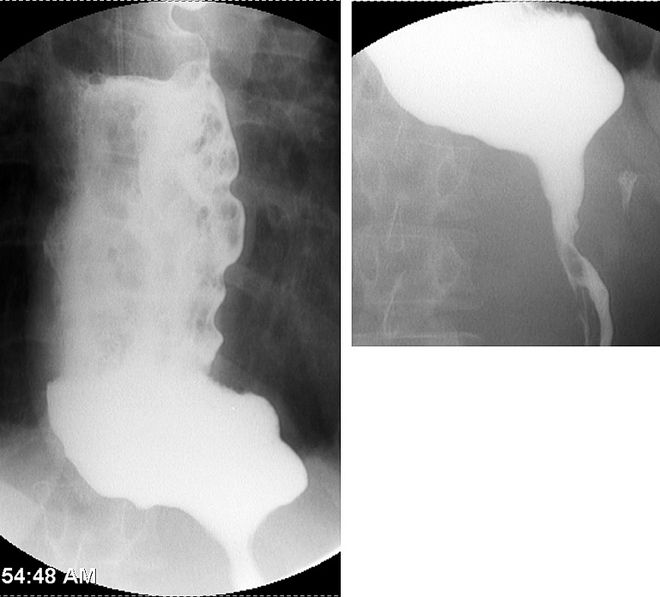

。术后颈部肿胀即刻消退,患者顺利拔除气管插管。钡餐造影(图4)及食管测压最终确诊贲门失弛缓症。

图4. 钡餐造影显示慢性贲门失弛缓症特征:重度扩张的“S型食管”(乙状结肠形),末端逐渐变细呈典型“鸟嘴征”[2]